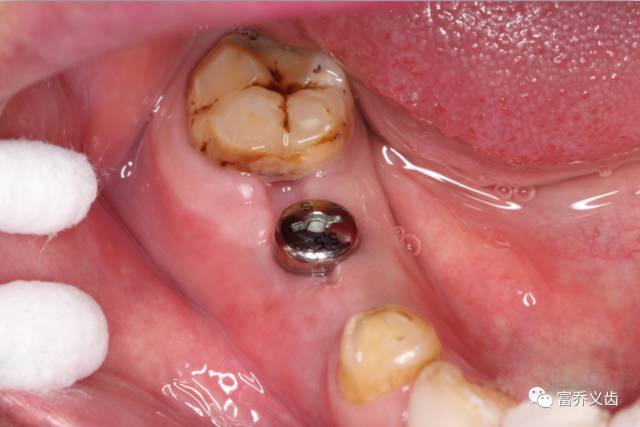

术后一个月照片